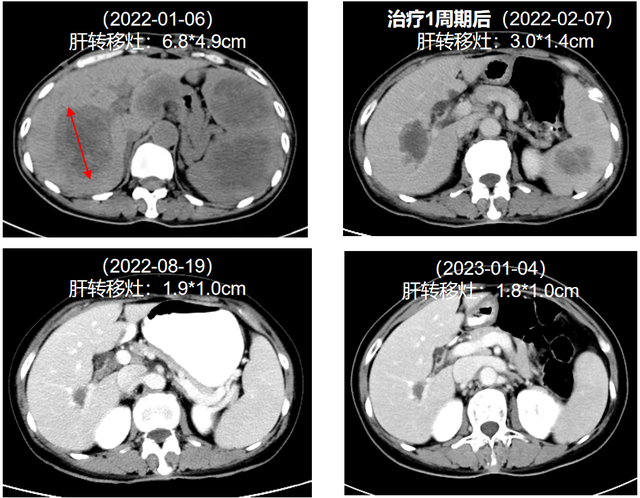

2022年1月7日,患者开始接受达拉非尼(150mg bid)+曲美替尼(2mg qd)一线治疗,联合双磷酸盐抗骨代谢治疗。治疗1周期(2022年2月7日)后,肝转移灶、脾转移灶和皮下转移灶缩小,肾盂转移灶消失。最新复查结果(2023年1月4日)显示,肝转移灶、脾转移灶稳定控制,病情持续控制中。

图2. 治疗前后肝转移灶变化